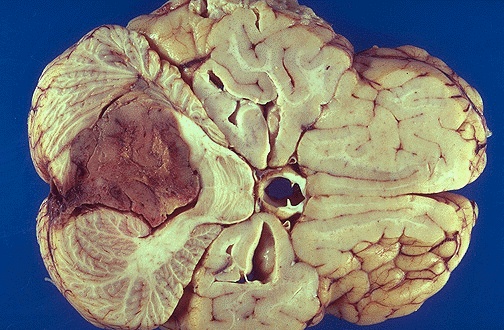

ويعتبر التهاب السحايا مرضا جرثومي حاد، يبدأ فجأة بارتفاع في درجة حرارة الجسم وصداع شديد وتصلب في الرقبة والظهر مع غثيان وقيء وطفح صغير الحجم على الجلد. وسرعان ما يتطور إلى حالة من الهذيان والضعف العام والغيبوبة، ثم الانهيار العام والصدمة. ويذكر أن معدل الاصابات بالتهاب السحايا، أوروبياً، يصل الى ألف حالة سنوياً.

عادة، يتم تشخيص هذا المرض بوجود الجراثيم الخاصة به، في الدم أو في سائل النخاع الشوكي أو في مسحات تؤخذ من الحلق. وتنتقل العدوى مباشرة عن طريق كل ما هو ملوث بها، وبينها الملابس. بالنسبة لفترة الحضانة، فانها تتراوح بين يومين وعشرة أيام. كما يتم عزل المريض، سريرياً، إلى أن تختفي تلك الجراثيم الموجودة في المسحات المأخوذة من الحلق.